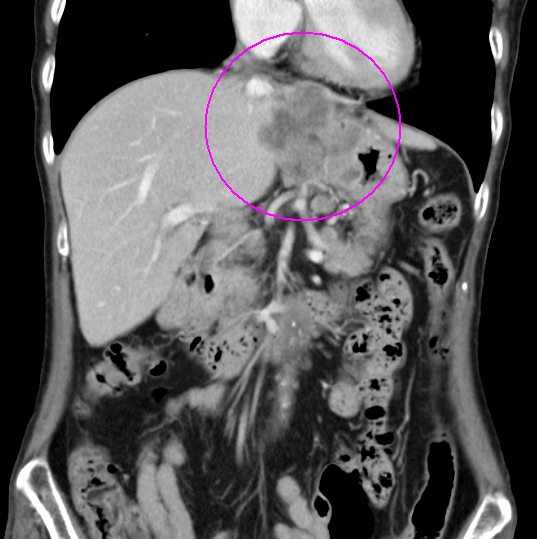

術前化学療法の例(造影CT画像)

治療前